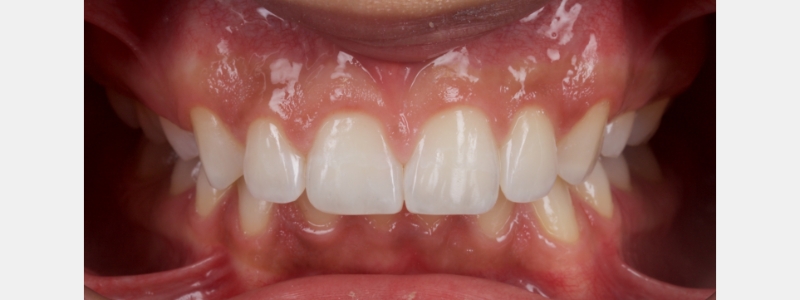

In this case, a young patient in his early 20s presents with discolored central incisors, multiple diastemas, and a canted incisal plane (Fig. 23).

A clear PVS stent was fabricated from a digital wax-up and filled with flowable composite (Fig. 24).

I prefer an opaque flowable composite for this application because a regular flowable composite tends to be quite translucent, making the underlying tooth structure visible, which distracts many patients. The flowable composite was polymerized, and the stent was removed.

The esthetics were assessed by the patient, and some adjustments were made to the distal line angles of the lateral incisors. When the patient was satisfied with the appearance, another sectional digital scan of the modified mock-up in the patient’s mouth was taken and stitched into the original scan to form the final mock-up (Figs. 25 and 26).